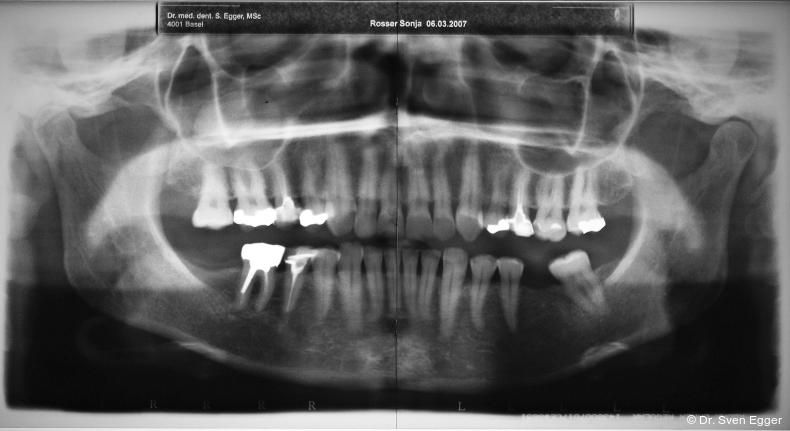

Parodontal zeigen sich keine Auffälligkeiten. Der CMD-Kurzbefund zeigte eine Druckdolenz im Bereich M. masseter und M. temporalis. Die KG sind unauffällig.Die Zähne 17, 26 sind elongiert, 37 ist nach mesial gekippt. Es liegt ein Tiefbiss vor.

Das OPG zeigt insuffiziente endodontische Versorgungen an 15, 25 und 46. Die Kieferhöhle rechts zeigt eine kirschgroße, kugelige Verschattung (Überweisung/Abklärung Kieferchirurgie).

- Sinusitis maxillaris rechts (Verdacht auf Mukozele)

- Revision der insuffizienten Wurzelfüllungen 15, 25 und 46. Bei Nichterfolg jeweils Extraktion, Ersatz durch Einzelzahnimplantat nach Abheilphase von zwei Monaten.

- Einzelzahnimplantate 047 und gegebenenfalls bei 15, 25 und 46 (bei erfolgloser WB-Revision).